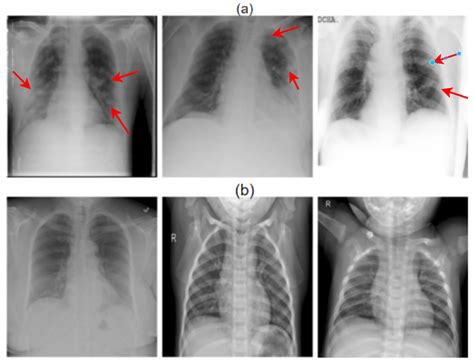

• Determining Severity: It helps the physician understand if the infection is limited to one lobe (lobar pneumonia) or spread throughout both lungs (bronchopneumonia).

• Detecting Complications: It helps identify potential issues such as pleural effusion (fluid buildup around the lungs) or abscesses that may require different treatment approaches.

When a radiologist reviews a Pneumonia X-ray, they are looking for specific indicators of disease. Healthy lungs on an X-ray typically appear black because they are filled with air, which does not block the X-ray beams. Conversely, infected tissue blocks these beams, leading to white areas on the film. These findings are often referred to in clinical reports as "infiltrates" or "consolidation."

Localized white patches (Consolidation) Indicative of active pneumonia infection

Cloudy shadows Possible interstitial inflammation or fluid

Blunted costophrenic angles Potential sign of pleural effusion (complication)